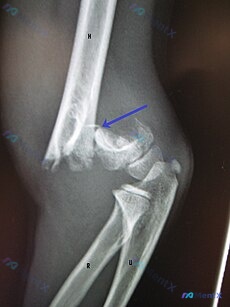

病例背景 最近整理到一份关于上肢创伤的病例资料,想和大家一起复盘一下其中的机制。 病史摘要 一名 5 岁男孩在全地形车事故中导致手臂骨折。急诊行复位术并使用了紧紧贴合的石膏固定。两周后,患儿再次就诊,表现为手腕和手部屈曲挛缩,手指被动伸展时会导致剧烈疼痛。 影像与查体线索 - X 光片:显示肱骨远端...